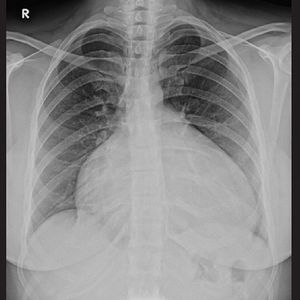

Cardiomegaly

X-Ray of a cheat showing a cardiomegaly. Look at the size of that heart !!!